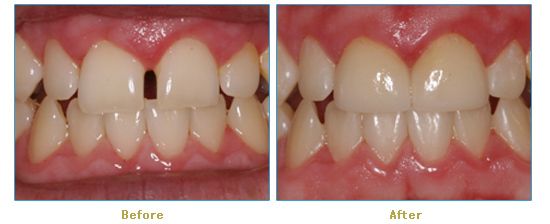

Dr. Cabianca has restored hundreds of smiles through the latest techniques in restorative and cosmetic dentistry. The following before and after photos document a few such cases in which Dr. Cabianca has replaced and reshaped teeth to produce wonderful smiles. Click on any of the images below to view larger versions of the photos.